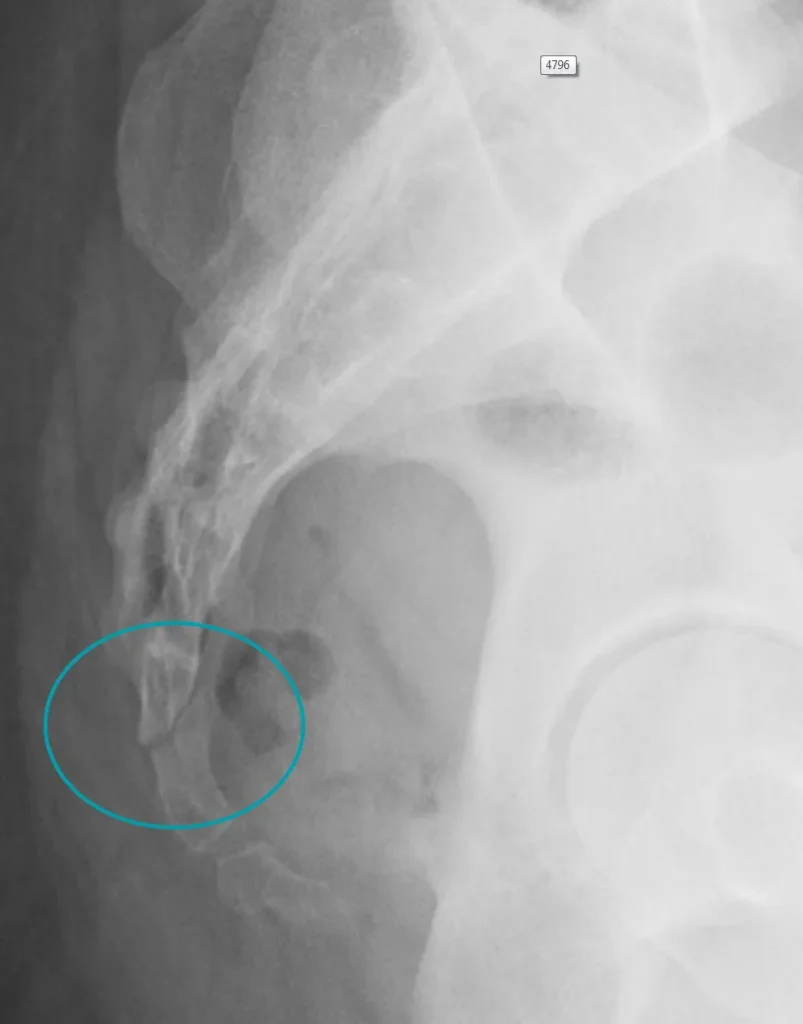

Od slikovnih pretraga najčešće se koriste:

- Rendgenska snimka (RTG) – pomaže u otkrivanju prijeloma ili iščašenja trtice.

- CT (kompjutorizirana tomografija) – prikazuje detaljnije koštane strukture i može otkriti tumore.

Ipak, kod mnogih pacijenata standardne slikovne metode, poput RTG-a, CT-a i MR-a, ne otkrivaju jasne abnormalnosti. Zato je za postavljanje dijagnoze često presudan temeljit klinički pregled i dobra anamneza, uz isključivanje drugih mogućih izvora boli u donjem dijelu kralježnice.